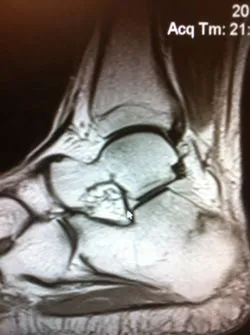

MRI imaging is excellent for diagnosing stress fractures. A T1 weighted image will show normal bone in a white color and edema and/or fracture lines in gray to black color (below left). T2 weighted imaged are the opposite and will show bone black and any fluid like swelling within the bone or throught a fracture as white (below right).